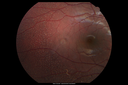

12 year old female She went last December for her regular checkup and spots were noted on the retina in the periphery. Her vision is fine and there is no family history of retinal disease. She has difficulty seeing at night and finding her way in a dark theater. VA OD: Dcc20/20-1 NccJ1+ VA OS: Dcc20/20 NccJ1+

Fundus Albipunctatusvista 962 veces12 year old female with normal vision. She has 4 siblings all of whom have either white spots or spots on IR. Genetic testing by parents was deferred.00000